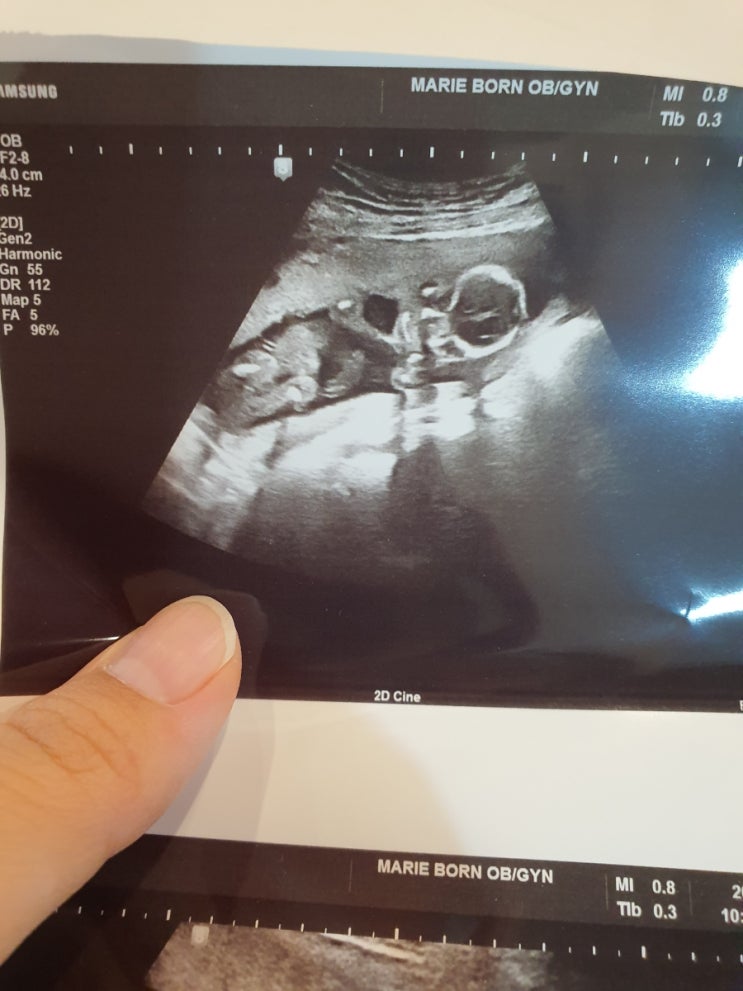

임신 6개월. 21주 정밀 초음파. 성별반전 없음. 몸무게 증가. 임산부 다리 쥐. 호주 엘레비트 임산부 영양제.

임신 6개월 일상 입덧이 사라진 6개월 안정기를 마음껏 누리고 있다. 배는 꽤 나온 티가 나는데 아직은 잘 ...